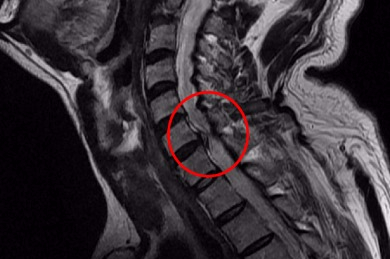

디스크의 수핵이 빠져나가거나 퇴행성 경추 척추증 및 경추관협착증 등으로 척수가 눌리게 되면 거의는 팔의 힘이 빠지는 느낌을 받을 수 있습니다.

목 디스크 증상으로 저림 현상을 겪으실 수 있다고 합니다. 이유는 디스크의 수핵이 빠져나가거나 퇴행성 경추 척추증등으로 척수가 눌리게 되는 만큼 팔의 힘이 빠지고 저린 경우가 많으므로져요. 척수가 눌린 강도에 따라서는 팔이 마비가 되기도 하며, 어지럼증을 또한 맛볼 수도 있어요.